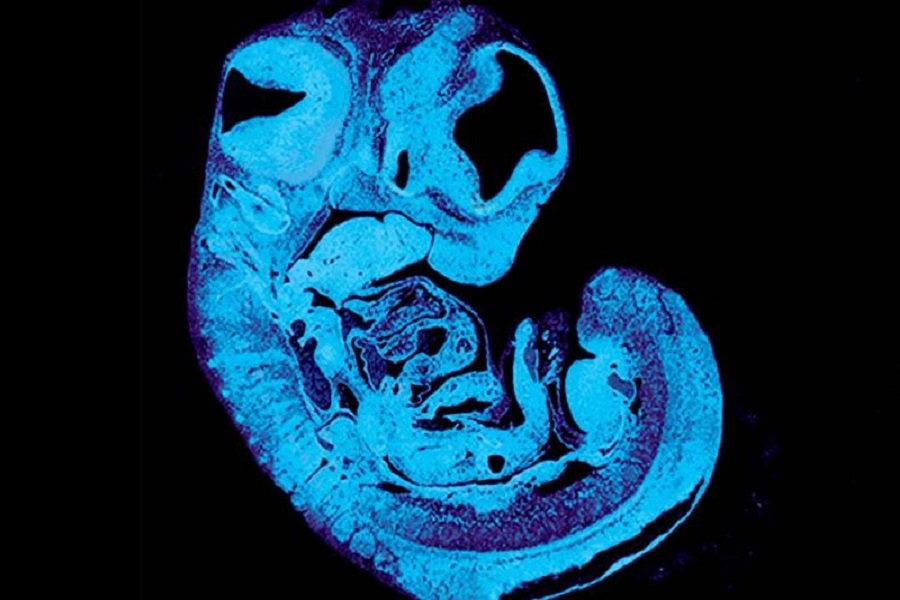

توصلت دراسة حديثة إلى أن جينات كل من الأب والأم تخوض صراعًا داخل الرحم على تغذية الجنين.

وأجرى الباحثون في جامعة كامبريدج بإنجلترا، تجارب على الفئران حددوا الإشارات التي ترسلها الأجنة للتحكم في إمداد المشيمة بالغذاء، وهو ما يمكن أن يساعد في تفسير سبب ضعف نمو بعض الأطفال في الرحم.

مع نمو الجنين، يحتاج إلى توصيل احتياجاته المتزايدة من الطعام للأم، يتغذى عن طريق الأوعية الدموية في المشيمة، التي تحتوي على خلايا من الأم والطفل.

في الفئران المعدلة وراثيًا، أظهر الباحثون كيف يُصدر الجنين إشارة لتشجيع نمو الأوعية الدموية داخل المشيمة. تسبب هذه الإشارة أيضًا تعديلات على خلايا أخرى في المشيمة للسماح لمزيد من العناصر الغذائية من الأم بالمرور إلى الجنين، مما يخلق "شد الحبل" بين الجينات الموروثة من الأب والأم، وفقًا لما ذكره الباحثون في الدراسة التي نشرتها مجلة "ديفلوبمنت سيل".